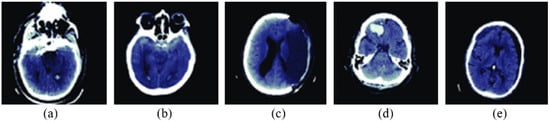

The proposed OGRU model’s performance is validated on a foreign database: RSNA 2019 brain CT hemorrhage database, which consists of 25,272 3D brain scans with 870,301 slices and a pixel size of . In this manuscript, the proposed OGRU model is re-trained on this database, and then the results are validated with different cross-folds. In the RSNA 2019 brain CT hemorrhage database, the 3D brain scans are labeled with the annotators using 5 brain hemorrhage label types intraparenchymal, epidural, intraventricular, subarachnoid, and subdural. Furthermore, the brain scans are collected from three institutions like Stanford University, Universidade Federal de Sao Paulo Institution, and Thomas Jefferson University Hospital. In the RSNA 2019 brain CT hemorrhage database, the annotators have no information about symptoms’ acuity, medical history, patient age, and prior examination. However, it is automatically labeled as intracranial hemorrhage, while a slice comprises at least one intracranial hemorrhage type. The sample acquired 3D brain scans are depicted in Figure 2.

Figure 2.

Sample acquired 3D brain scans, (a) intraparenchymal, (b) epidural, (c) intraventricular, (d) subarachnoid, and (e) subdural.